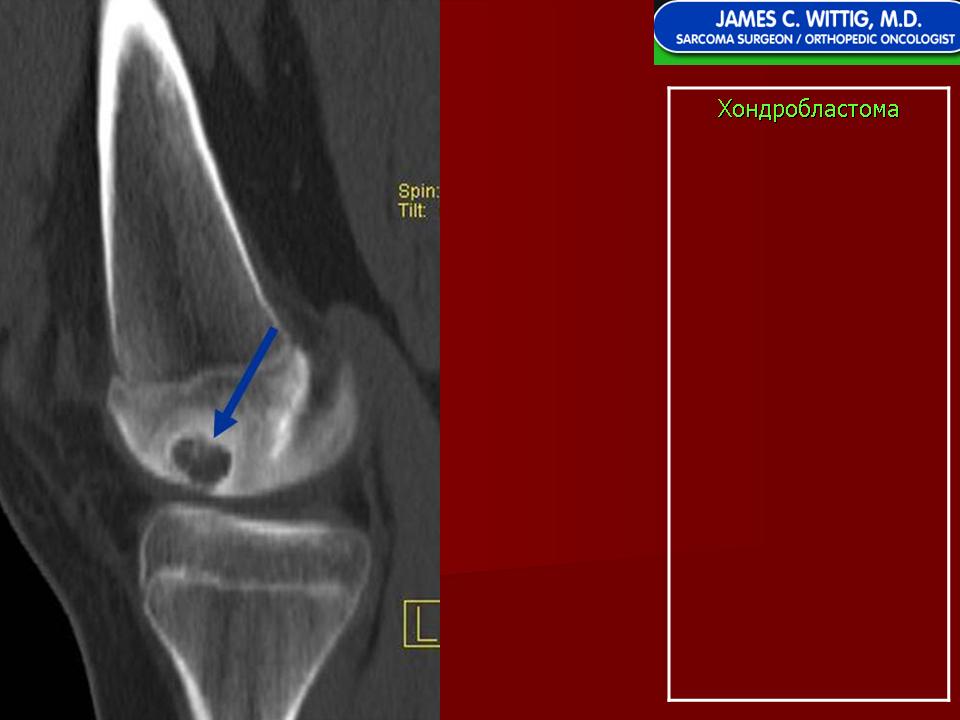

Хондробластома — это редкая доброкачественная опухоль, локализующаяся, главным образом, в эпифизе и отличающаяся своеобразным клеточным составом. Ткань новообразования представлена овальными, округлыми и веретеновидными клетками, напоминающими незрелые хондроциты (хондробласты). Зрелый гиалиновый хрящ определяется лишь в некоторых опухолях. Возраст больных варьирует. Мужчины поражаются в два раза чаше женщин. Пациенты предъявляют жалобы на боли в течение нескольких месяцев или лет, у некоторых больных определяются внутрисуставной выпот, припухлость и ограничение движений. Наиболее типичная локализация опухоли — проксимальные эпифизы плечевой и большеберцовой костей, а также дистальный эпифиз бедренной кости. У 20 % больных опухоль развивается в плоских или коротких трубчатых костях, преимущественно в пяточной и таранной. Изредка поражаются кости лицевого черепа, в том числе височная. В большинстве случаев новообразование выходит за пределы эпифиза и распространяется на метафиз. На фоне остеолиза обнаруживаются рассеянные участки обызвествления в виде пунктирных линий, а также разреженный трабекулярный рисунок. Хондробластома, как правило, не выходит за пределы кости, но изредка проникает в полость сустава. В процессе роста опухоли иногда возникает вторичная аневризматическая костная киста.

Рентгенологически хондробластома представляет собой сравнительно большой (2-4 см) очаг округлой формы, четко отграниченный от окружающей кости склеротической каймой. На фоне очага в большинстве случаев, но не обязательно определяются плотные включения, напоминающие хлопья ваты.

Рентгенологическая картина. Хондробластома выглядит как небольшой, от 3 до 6 см литический очаг, центрально или эксцентрично расположенный, с четкими контурами, занимающий около половины площади эпифизарной зоны. Хондробластома плоских костей и мелких трубчатых костей больших размеров, может сопровождаться припухлостью мягких тканей, вздутием кости и периостальной реакцией. Распространение процесса на метафизарную зону встречается часто.